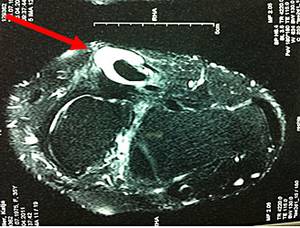

Der Knick-Senkfuß beim Erwachsenen entwickelt sich in der Regel durch eine schmerzhafte Insuffizienz der M. Tibialis posterior Sehne. Die Sehne verläuft an der Innenseite unter den Fuß und stützt das Fußlängsgewölbe ab. Sie sorgt beim Gehen für die notwendige Stabilität um sich richtig abstoßen zu können. Insbesondere Übergewicht und Verschleiß dieser Sehne führen zum Bild der klassischen Knick-Senkfußdeformität. Es kommt zu kleinen Teileinrissen auf dem Boden einer chronischen Tendinitis (Sehnenentzündung) oder Tenosynovitis (Sehnenschleimhautentzündung).

Ein akutes Trauma mit kompletten Riss der Sehne mit nachfolgendem Kraftverlust sind die Ausnahme.

Abb.1: Die MRT zeigt eine chronische Entzündung der Sehne mit Erguss (Pfeil).